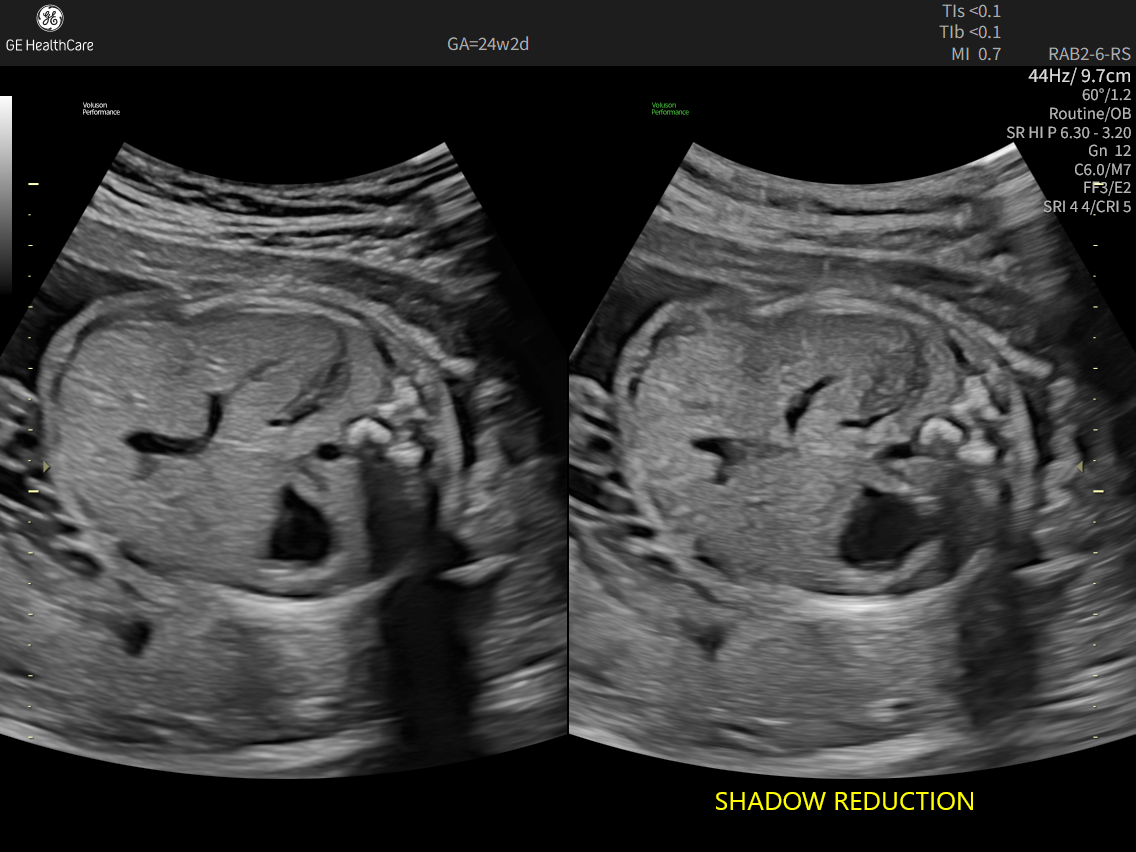

Image quality is everything in ultrasound.

The Voluson Performance series delivers high-resolution, detailed imaging with one-touch optimization for effortless scanning helping you deliver quick, confident answers across a wide range of patients.